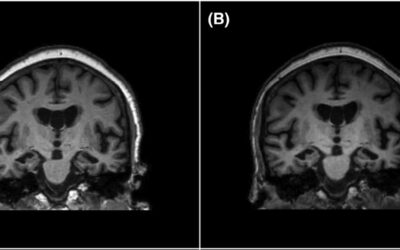

Хвороба Альцгеймера (ХА) — найпоширеніша причина деменції у світі: вона відповідальна за 60–80% усіх випадків. Але за статистикою стоять живі люди — з їхніми спогадами, звичками,...

Міжнародна команда вчених із Китаю та Іспанії розробила наночастинкову терапію, яка на 45% зменшує накопичення амілоїду в мозку мишей з експериментальною хворобою Альцгеймера та повністю...